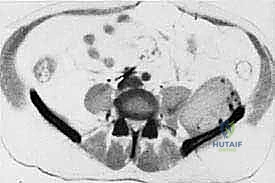

* CT with Intravenous Contrast and 3D Reconstruction (FIG 3): This is our workhorse for assessing bone involvement, destruction, and the critical relationship between the tumor and major pelvic blood vessels. It reveals any distortion of the pelvic anatomy and guides resectability. Figure 3A clearly shows extensive bone destruction and tumor extension into the pelvis and gluteal region. Figure 3C highlights an extensive tumor on the medial aspect of the ilium with destruction of the inner table.